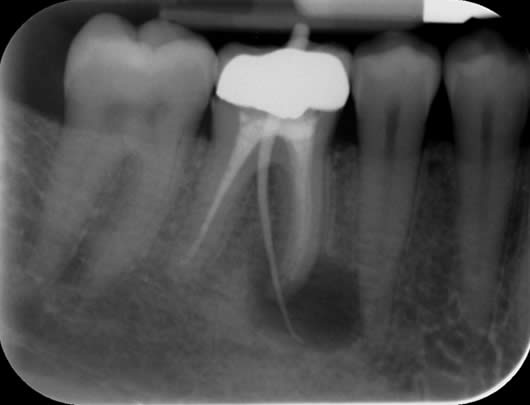

Case 2: Root canal treatment – the elusive MB2 canal.

In approximately 90% of upper first molars there are four root canals. The fourth canal (MB2) is difficult to locate and can be very challenging to negotiate to its end. It is a very common occurrence that this canal is missed during treatment and this can lead to failure. We use a dental microscope, which magnifies the tooth and assists us in locating this canal. We then use a series of tiny instruments in a specific technique, honed over many hours of practice, to negotiate to the end of the canal. This case shows the filling of all four canals.

Pre-operative radiograph UR6

Post-operative radiograph UR6